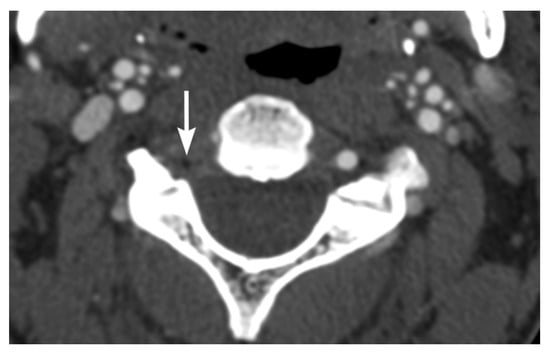

3. Imaging Findings of Arterial Injury